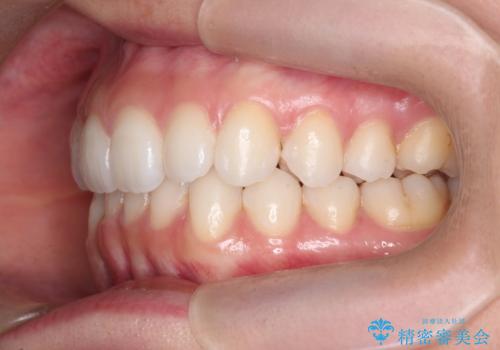

歯を抜かずに後方移動で達成する、前突感の改善

- 前歯が出っ歯のように見えることの改善を求めて来院されました。

当初、セラミックによる治療をご希望されていましたが、相談の結果矯正治療を選択されることとなりました。

通常口元の突出感の改善を行うには小臼歯の4本抜歯が検討されますが、歯のガタ付きが下顎前歯に限定していることから

下顎前歯を1本だけ抜去を行い、上顎の歯は可及的にマイクロインプラントを用いた後方移動を行い口元の印象の改善を計画することとなりました。

マイクロインプラントを用いてしっかりと後方移動を行ったことで前歯の角度は改善され、口元もすっきりと仕上げることができました。